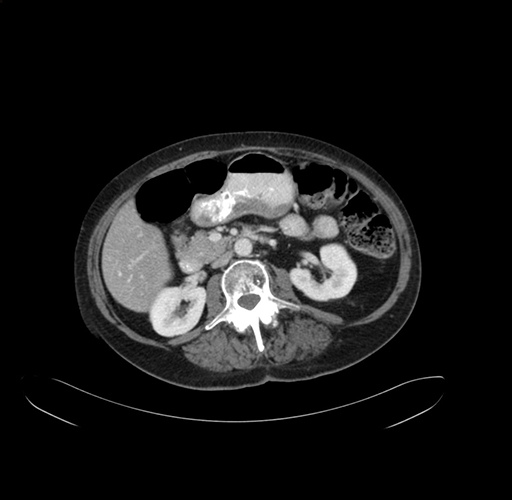

Pre-Chemo: Axial Venous

Axial Venous